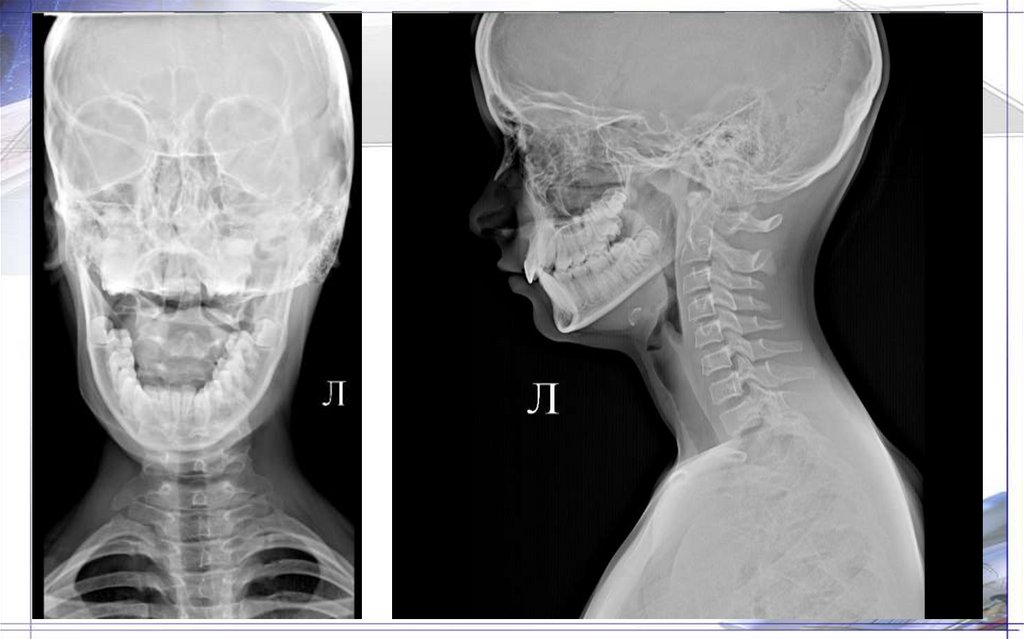

Рентгенограмма верхних

шейных позвонков в прямой

проекции

1. Ножка дуги шейного позвонка

2. Дуга осевого позвонка

3. Остистый отросток шейного позвонка

4. Боковые массы атланта

5. Зуб осевого позвонка

6. Верхняя суставная поверхность

второго шейного позвонка

7. Передняя дуга атланта

8. Задняя дуга атланта

Рентгенограмма шейного

отдела позвоночника в

прямой проекции

1. Межпозвонковое пространство

2. Полулунные отростки

3. Ножка дуги позвонка

4. «Боковые массы» тел позвонков

5. Дуга позвонка

6. Остистые отростки

7. Подъязычная кость

8. Щитовидный хрящ

Рентгенограмма шейного отдела

позвоночника в боковой

1. Атлант

2. Остистый отросток

3. Дуга позвонка

4. Ножка дуги шейного позвонка

5. Межпозвонковое пространство

6. Верхний суставной отросток

7. Нижний суставной отросток

8. Проекция позвоночного канала

9. Тело позвонка

10. Превертебральные мягкие ткани

11. Реберно-поперечные отростки шейного

позвонка